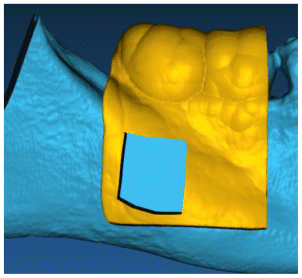

Case planning was done on Realguide 5.0 (3diemme, Varese, Italy). (Figure 9,10)

Two tooth-supported guides were created, one for implant (Esthetic Line-EL®, C-Tech, Bologna, Italy) placement and one for graft harvest. They were 3D printed with Mono X2 (Hong Kong Anycubic Technology Co., Hong Kong, China).